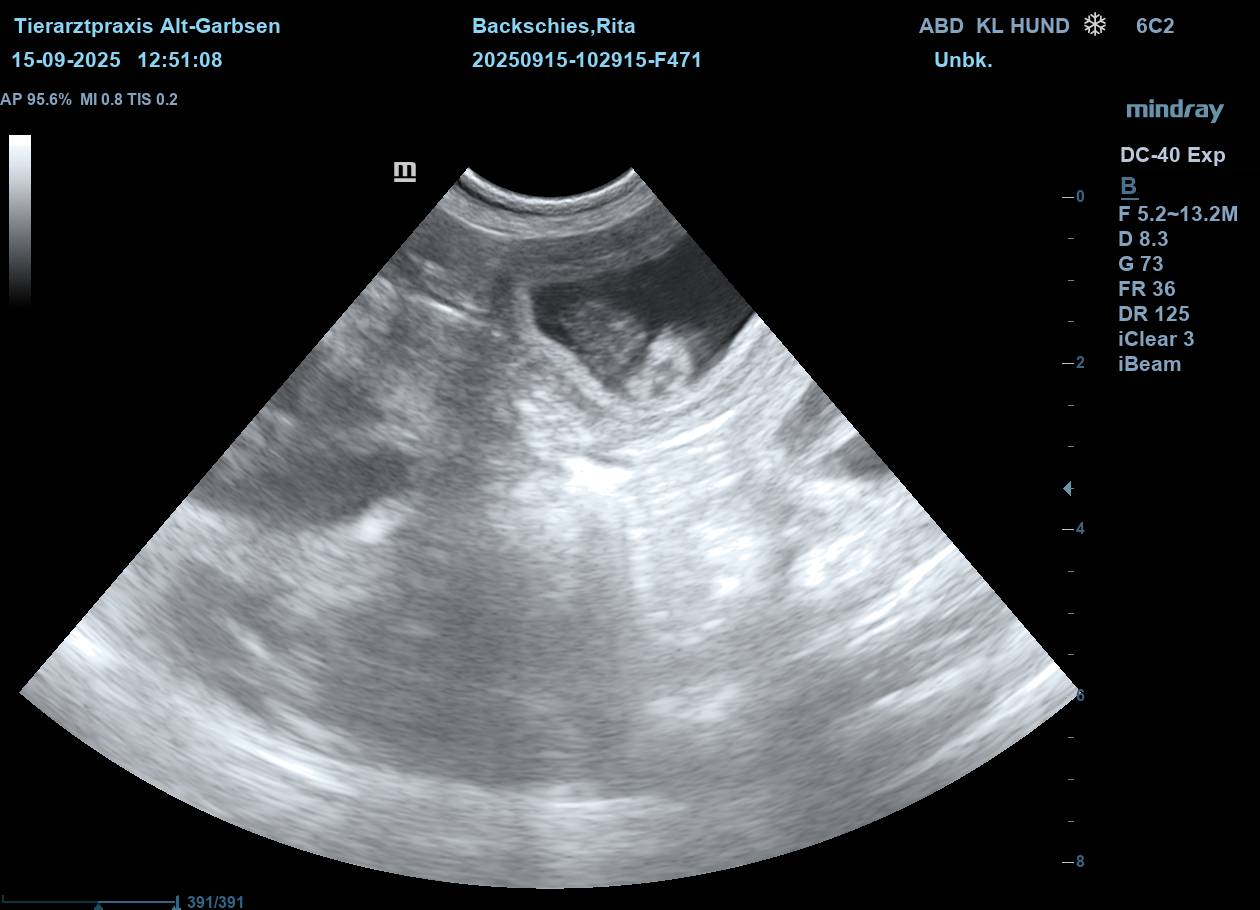

| Mo, 15.09.2025 | Es bahnt sich was an… der S-Wurf aus dem Zwinger Vom Lahberg FCI ist in die Produktion gegangen. Die Verpaarung am 17.08.2025 von Julissa Lisant Ingrid für Wambachtal „Rita“ und Kuddel vom Lahberg FCI war erfolgreich.🌿 Wir dürfen gespannt sein. In den nächsten Wochen werden wir dann Bilder vom wachsenden Babybauch posten. ![]() ![]() ![]() ![]() ![]() Jetzt heißt es mal wieder abwarten, beobachten, Däumchen drehen und hoffentlich bald freuen. |